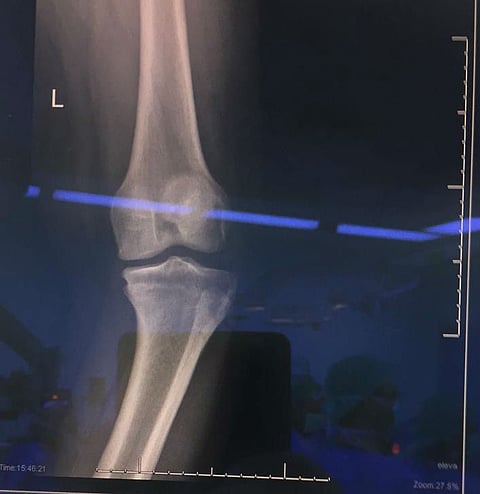

نجح قسم العظام بمستشفى الملك عبدالعزيز بجدة، في إجراء جراحة ناجحة لشاب في العقد الثاني من العمر يعاني من تقوس بارز في عظام الساق، وتَطَلّب ذلك إجراء عملية واحدة خلاف العمليات المألوفة، والتي تعتمد على التعديل التدريجي بواسطة جهاز تثبيت خارجي يبقى ملازمًا للمريض لمدة لا تقل عن ستة أشهر.

وأوضح استشاري جراحة العظام بمستشفى الملك عبدالعزيز بجدة الدكتور محمود الصالحي قائلًا: إن الشاب تمكّن من استعادة استقامة ساقيه بعد استخدام جهاز التثبيت الخارجي؛ حيث كان يراجع العيادة الخارجية بسبب معاناته من تقوس الساقين، وبعد إجراء الفحوصات الطبية الدقيقة والإشعاعية والمخبرية اللازمة، يتم البدء بالخطة العلاجية من خلال تقنية تثبيت الجهاز الخارجي.

وأضاف: الطريقة التقليدية لعلاج مثل تلك الحالات تتم عبر التدخل الجراحي لإيقاف صفائح النمو في الجهة التي يحدث بها التقوس بشكل يدوي؛ ولكنها قد لا تنجح في كل الحالات، وقد يستمر التقوس أكثر؛ مؤكدًا استعادة الشاب لممارسة حياته الطبيعية وتمتعه بصحة جيدة ولله الحمد.